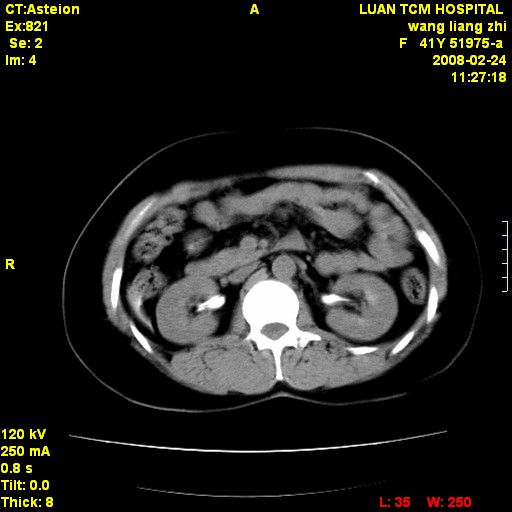

以下是引用dyqct在2009-8-23 16:17:00的发言:[br]考虑:1、造影剂进入腹腔、结肠旁沟、肝周;[br] 2、子宫明显增大(腺肌增生症?);[br] 3、膀胱显影是由于造影剂吸收后经肾分泌进入膀胱的;[br] 4、建议mri检查子宫。